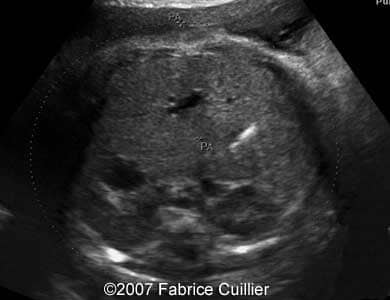

A 30-year-old patient, G3P2, was referred to our clinic at 36 weeks of gestational age after hyperechoic foci were seen in the fetal gallbladder on ultrasound. 13- and 22-week sonographic examinations were unremarkable. The 36-week ultrasound evaluation was normal except for an elongated echogenic mass seen in the gallbladder (Images 1A, 1B, 1C, 1D). Neither ascites nor hydrops were seen. The gallbladder appearance was identical on sonographic re-evaluation at 37 weeks GA (Images 3A, 3B). At 38 weeks of gestational age, a healthy female infant weighing 3200 g was born. There was no evidence of hematologic incompatibility, sepsis, or jaundice. Laboratory values including those for the cystic fibrosis gene, hemoglobinopathy, and liver functions were normal. On the fifth day of life, ultrasound was performed, showing a gallbladder of normal size containing several gallstones (Images 5A, 5B, 5C, 5D).

Images 1C, 1D. Transverse abdominal section at 36 weeks of gestational age through the fetal abdomen demonstrating a long, non-shadowing echogenic mass within the gallbladder.

1C

1D